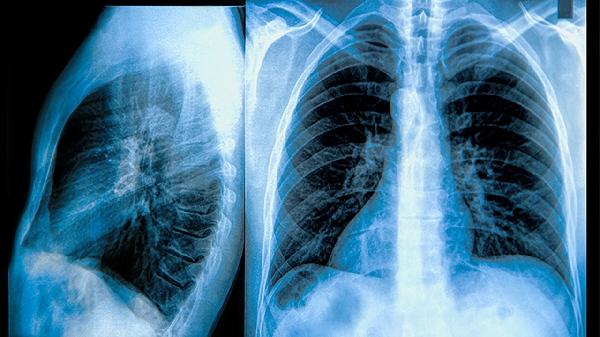

3、极少数情况下,肺钙化灶可能与某些肿瘤相关,但钙化本身并不是癌症的直接表现。需要通过影像学检查如CT和医生评估进一步明确诊断。

4、对于无症状的肺钙化灶,通常无需治疗,但建议定期复查胸部影像,以监测钙化灶的变化。